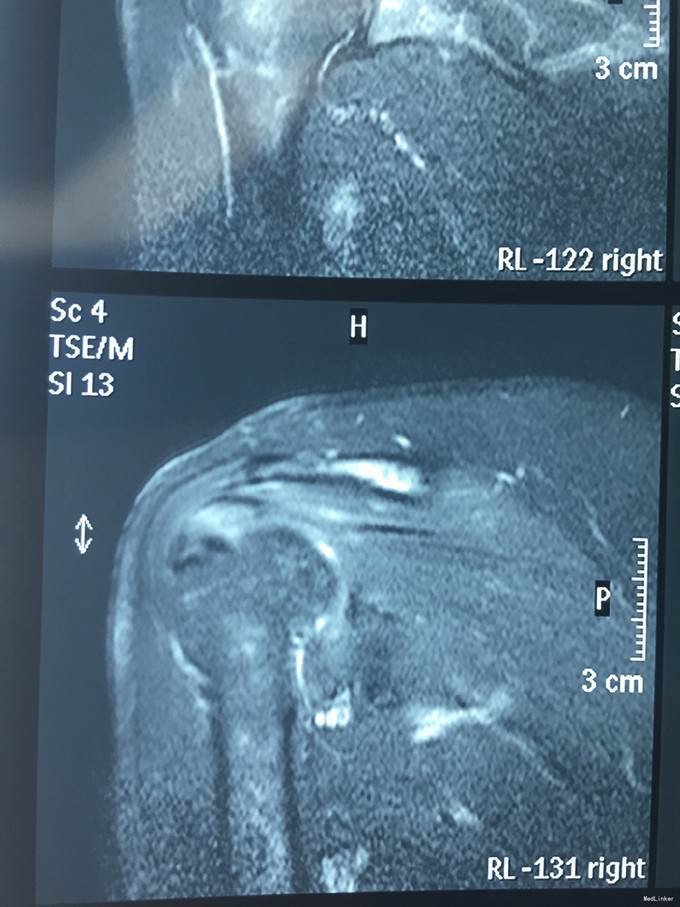

主诉:右肩疼痛5月,加重伴活动受限2月余。 现病史:患者,女性,45岁。5月前无明显诱因下出现右肩关节疼痛不适症状,偶伴有夜间痛,经休息等保守治疗后现疼痛症状略缓解。后患者至外院就诊,予口服药物等保守治疗,效果不佳,且有加重趋势。2月余前患者自觉右肩疼痛较前明显,伴活动受限。外院行MRI检查示:右肩关节内积液、右肩峰骨质增生、右肩袖肿胀、右肩盂唇信号异常。后患者来我院就诊,查右肩X线示:右肩峰前外侧见一骨性突起。门诊结合病史及体征,诊断“右肩峰下撞击综合症、右肩峰占位”收入院,行进一步治疗。

查体:右肩关节周围肌肉萎缩,右肩周压痛(+),右肩前方压痛(+),无明显肿胀。右肩关节主被动活动度明显受限,Hawking征(+),Neer征(+),Jobes征(-),Speed(+),O’brein征(-),Drop Arm(-)、熊抱试验(-)。外展肌力(Ⅳ)级。双上肢感觉正常。 辅查:见现病史,图片见下。

入院诊断:右肩峰下撞击综合症、右肩峰占位 治疗:右肩关节镜下肩峰成形,占位切除术